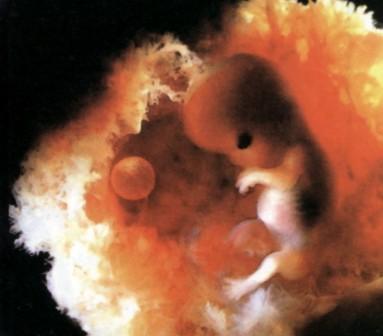

Találtam egy édes fotót, kb. ekkora most a pocaklakóm. Édes! :) Kép Manóka